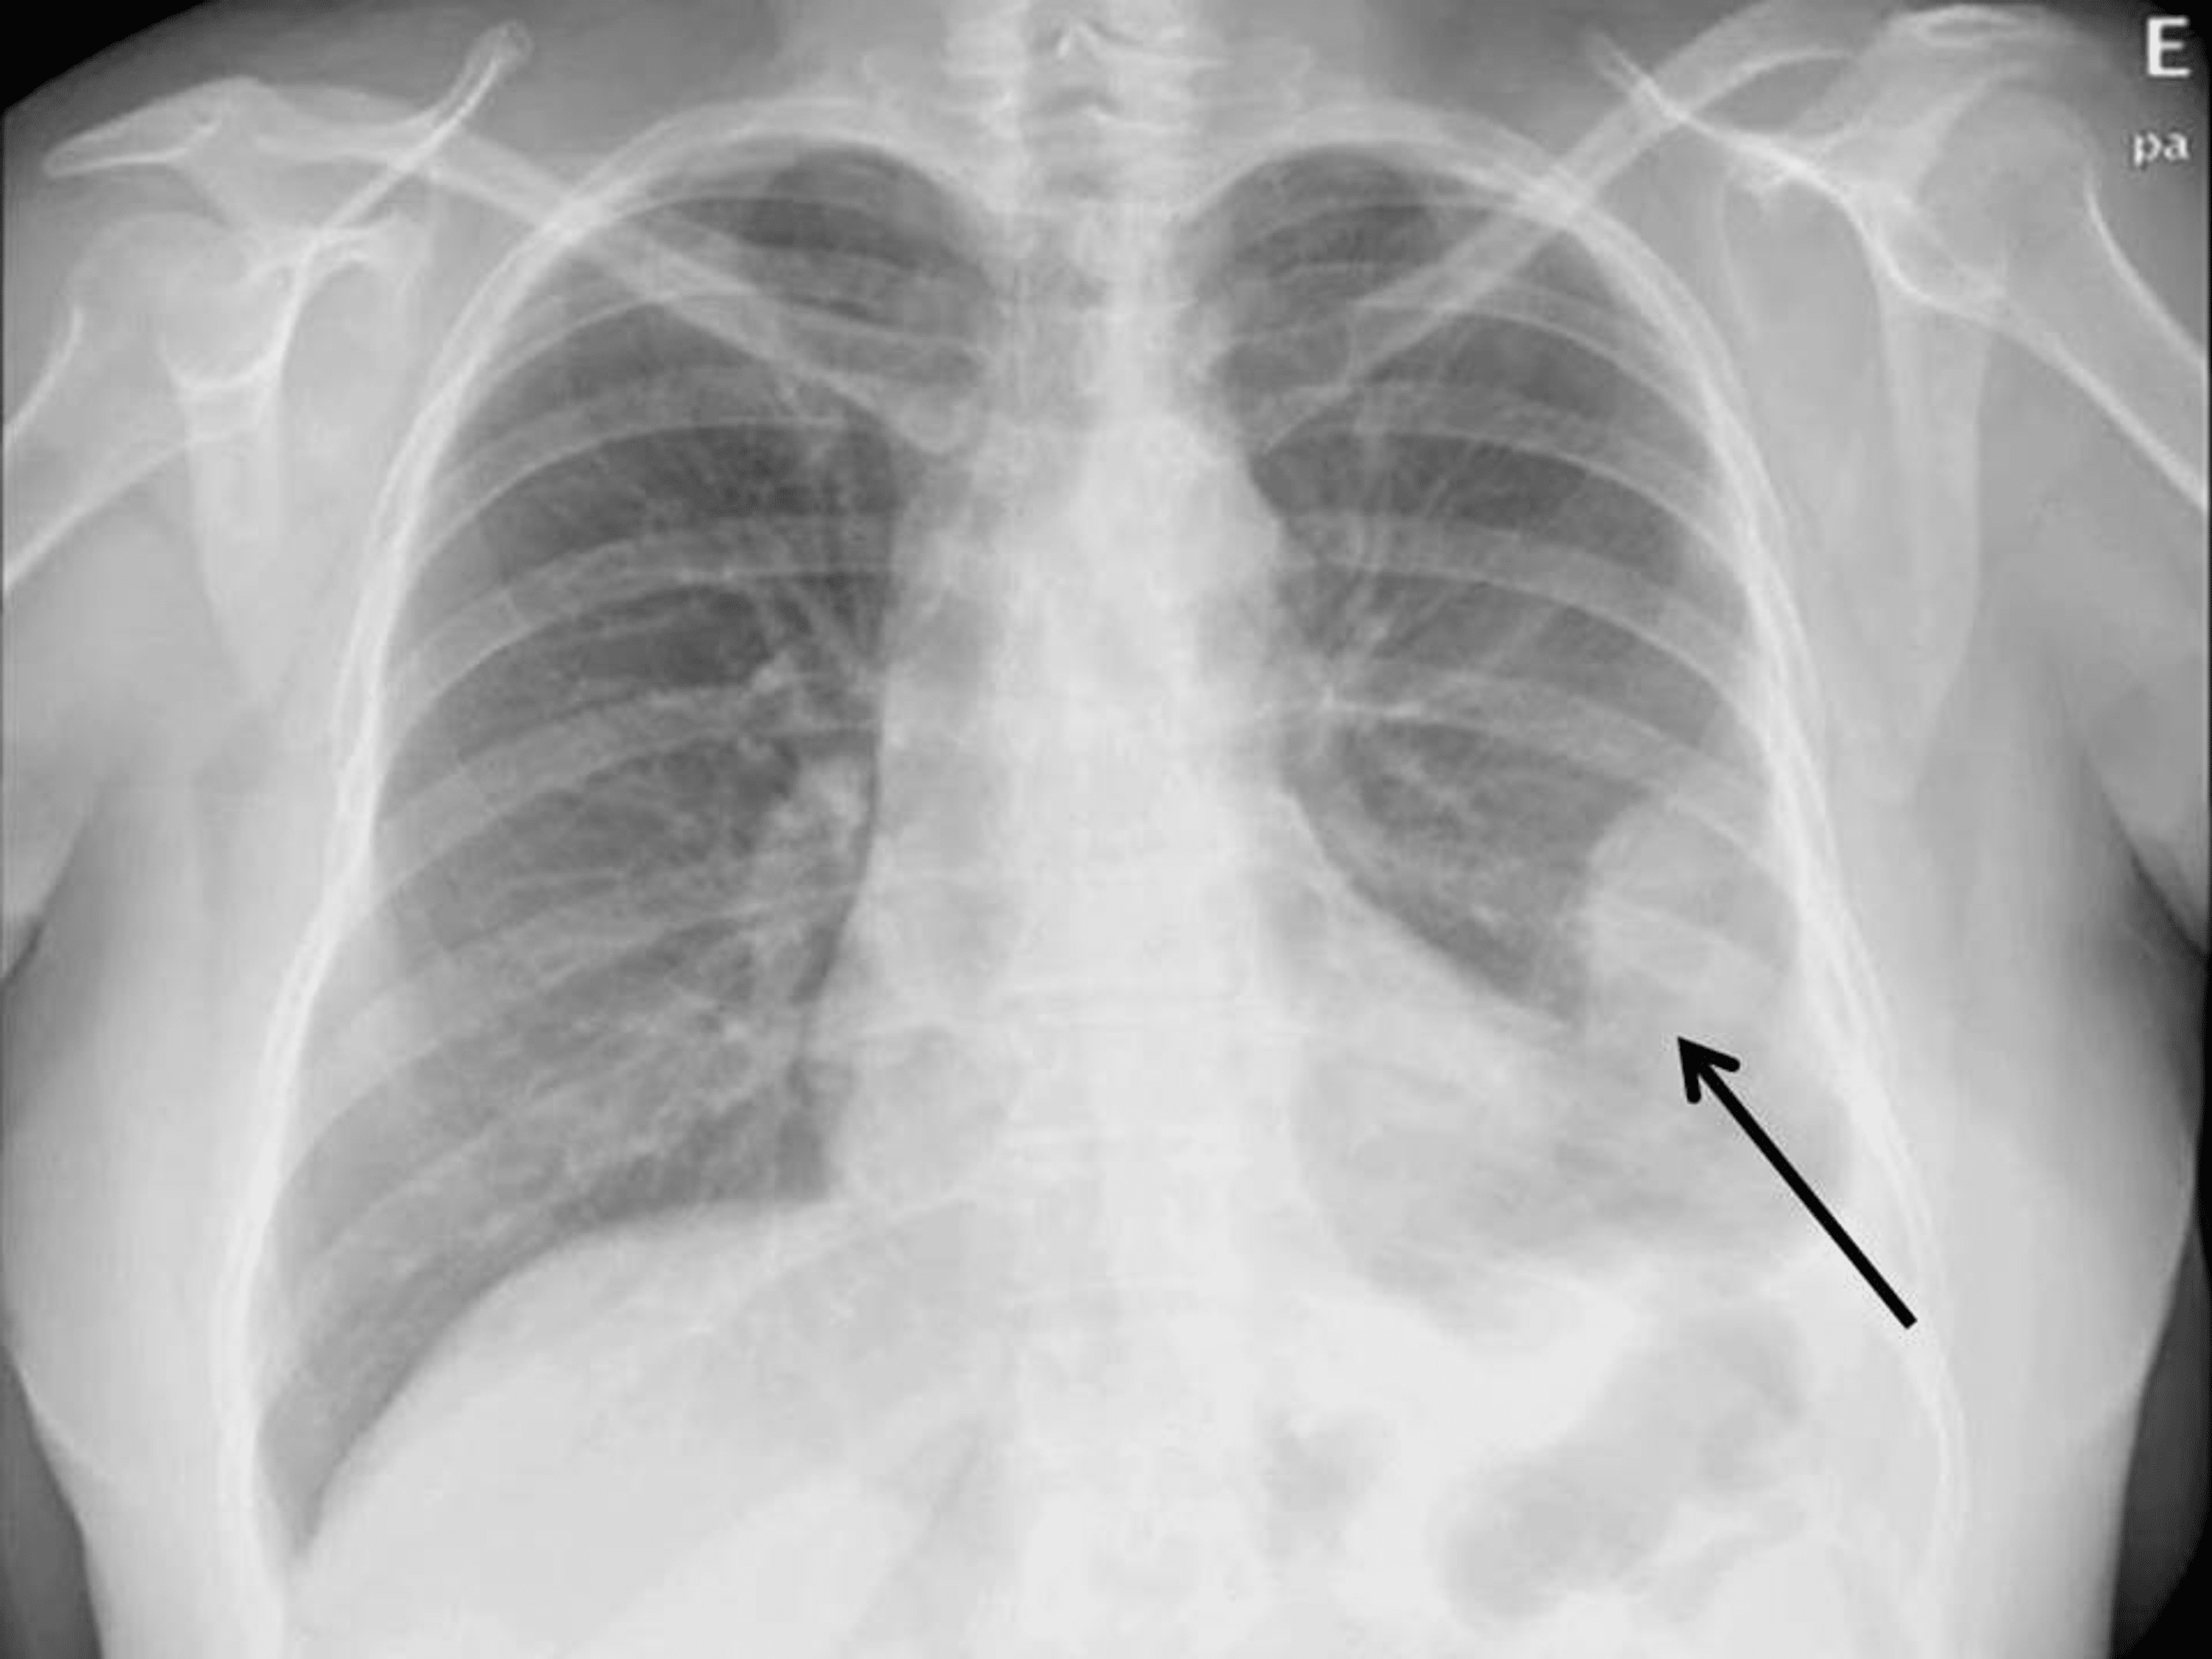

A) Shows the chest xray of a mesothelioma patient with a trapped lung Can A Chest X-Ray Show Mesothelioma It can also show up a rim of solid. That test may be repeated, or existing films may be. They can identify abnormalities in the chest. Typically, the first imaging test used when mesothelioma is suspected. This is often the first test done to look for problems in the lung. Findings that might suggest mesothelioma include an. Can A Chest X-Ray Show Mesothelioma.